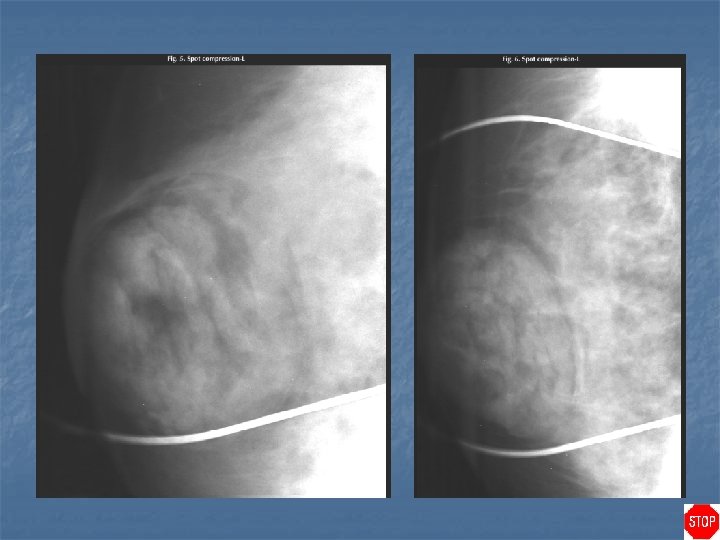

Case directory Sebaceous cyst (epidermal inclusion cyst) n n n Round, smoothly bordered mass that often abuts the skin surface Mass projects into the subcutaneous tissues rather than out from the skin surface Tangential view of the mass demonstrates that it is located within the skin